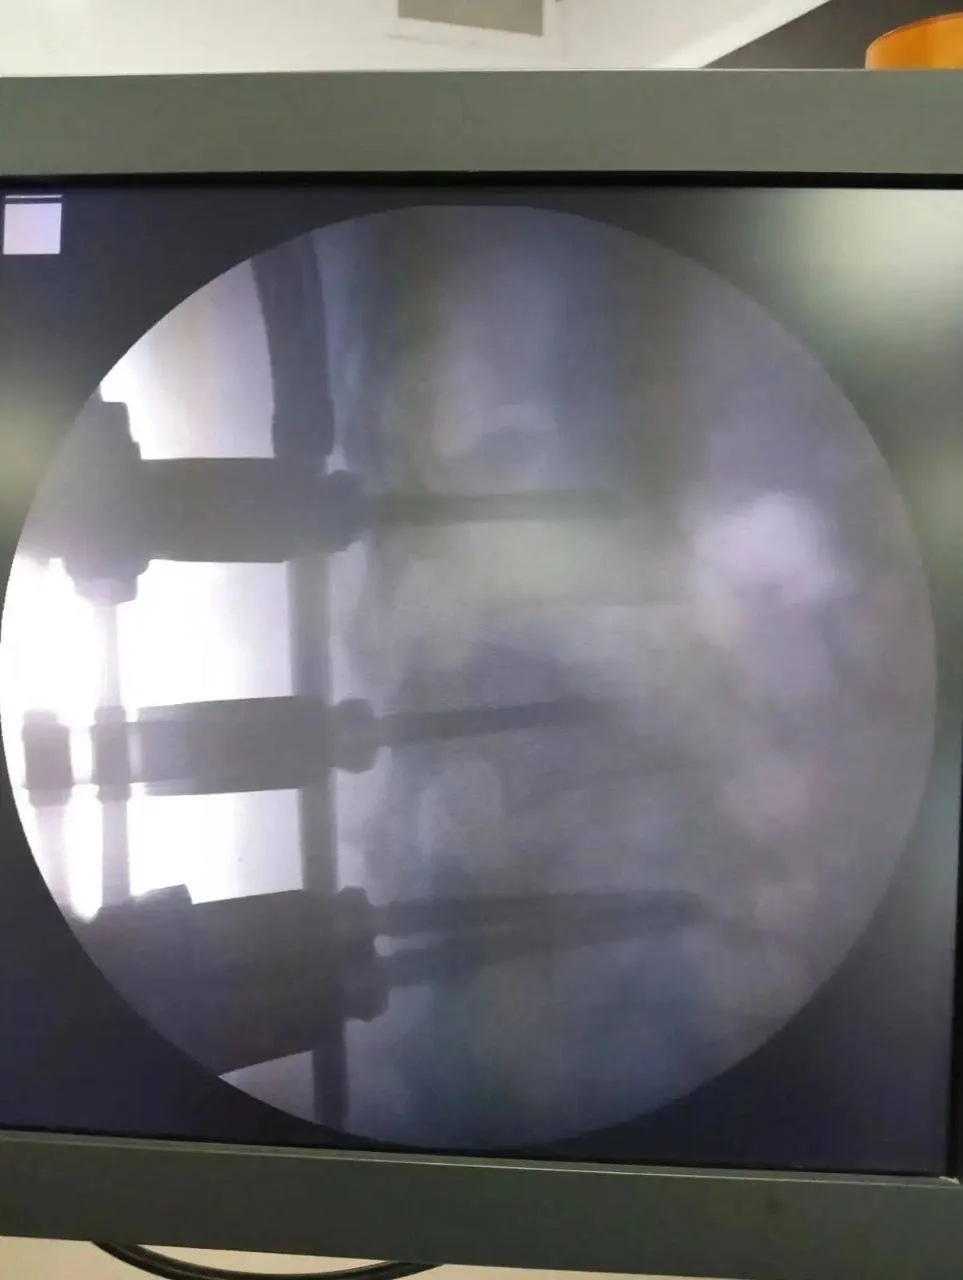

⚡ В Октябрьском врачи восстановили ампутированное ухо

В городскую больницу № 1 Октябрьского ночью поступил пациент с ампутированным участком ушной раковины. Требовалась немедленная операция.

Оперировал пациента оториноларинголог Николай Забелин, удостоенный в этом году звания «Лучший врач года». Ассистировала ему высококвалифицированная операционная медицинская сестра Заррина Назмутдинова.

Операцию провели с использованием микроскопической техники, что позволило врачу максимально точно восстановить анатомическую структуру ушной раковины. Команда медиков успешно реимплантировала ампутированный участок уха.

После операции пациента ждала реабилитация: ухо прижилось, и пациент смог вернуться к нормальной жизни, сообщили в соцсетях горбольницы № 1.